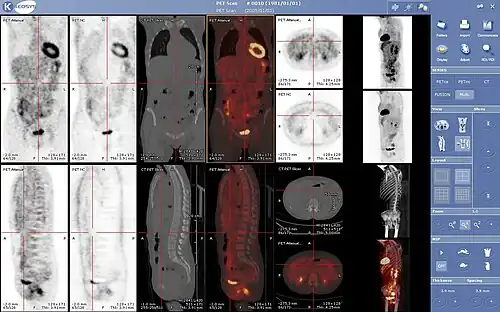

F-FDG (fluorodeoxyglucose). The normal brain and kidneys are labeled, and radioactive urine from breakdown of the FDG is seen in the bladder. In addition, a large metastatic tumor mass from colon cancer is seen in the liver.

PET scanning with the radiotracer [18F]fluorodeoxyglucose (FDG) is widely used in clinical oncology. FDG is a glucose analog that is taken up by glucose-using cells and phosphorylated by hexokinase (whose mitochondrial form is significantly elevated in rapidly growing malignant tumors).[4] Metabolic trapping of the radioactive glucose molecule allows the PET scan to be utilized. The concentrations of imaged FDG tracer indicate tissue metabolic activity as it corresponds to the regional glucose uptake. FDG is used to explore the possibility of cancer spreading to other body sites (cancer metastasis). These FDG PET scans for detecting cancer metastasis are the most common in standard medical care (representing 90% of current scans). The same tracer may also be used for the diagnosis of types of dementia. Less often, other radioactive tracers, usually but not always labelled with fluorine-18 (18F), are used to image the tissue concentration of different kinds of molecules of interest inside the body.

A typical dose of FDG used in an oncological scan has an effective radiation dose of 7.6 mSv.[5] Because the hydroxy group that is replaced by fluorine-18 to generate FDG is required for the next step in glucose metabolism in all cells, no further reactions occur in FDG. Furthermore, most tissues (with the notable exception of liver and kidneys) cannot remove the phosphate added by hexokinase. This means that FDG will remain trapped in any cell that takes it up until it decays, since phosphorylated sugars, due to their ionic charge, cannot exit from the cell. This results in intense radiolabeling of tissues with high glucose uptake, such as the normal brain, liver, kidneys, and most cancers, which have a higher glucose uptake than most normal tissue due to the Warburg effect. As a result, FDG-PET can be used for diagnosis, staging, and monitoring treatment of cancers, particularly in Hodgkin lymphoma,[6] non-Hodgkin lymphoma,[7] and lung cancer.[8][9][10]